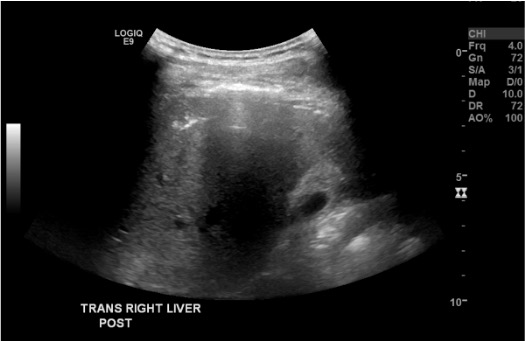

View post-biopsy US

Post-biopsy ultrasound of right liver showing expected echogenic tract